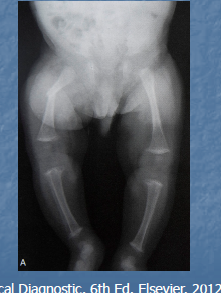

Rachitisme

= Défaut de minéralisation de la matrice osseuse au niveau du cartilage de croissance (Chez l’enfant en croissance)

Poignets

Genoux

Jonctions costochondrales

Rachitisme à la radio